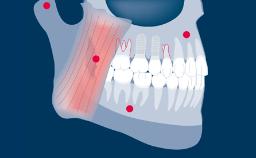

When implants have been placed and are restored with the final prostheses, certain principles have to be followed to achieve a good fit and long-term success of the prosthesis.

It is therefore important to have a protocol to ensure the correct steps are followed so as to minimize the risk of complications and to be able to verify that the procedure has been carried out correctly.